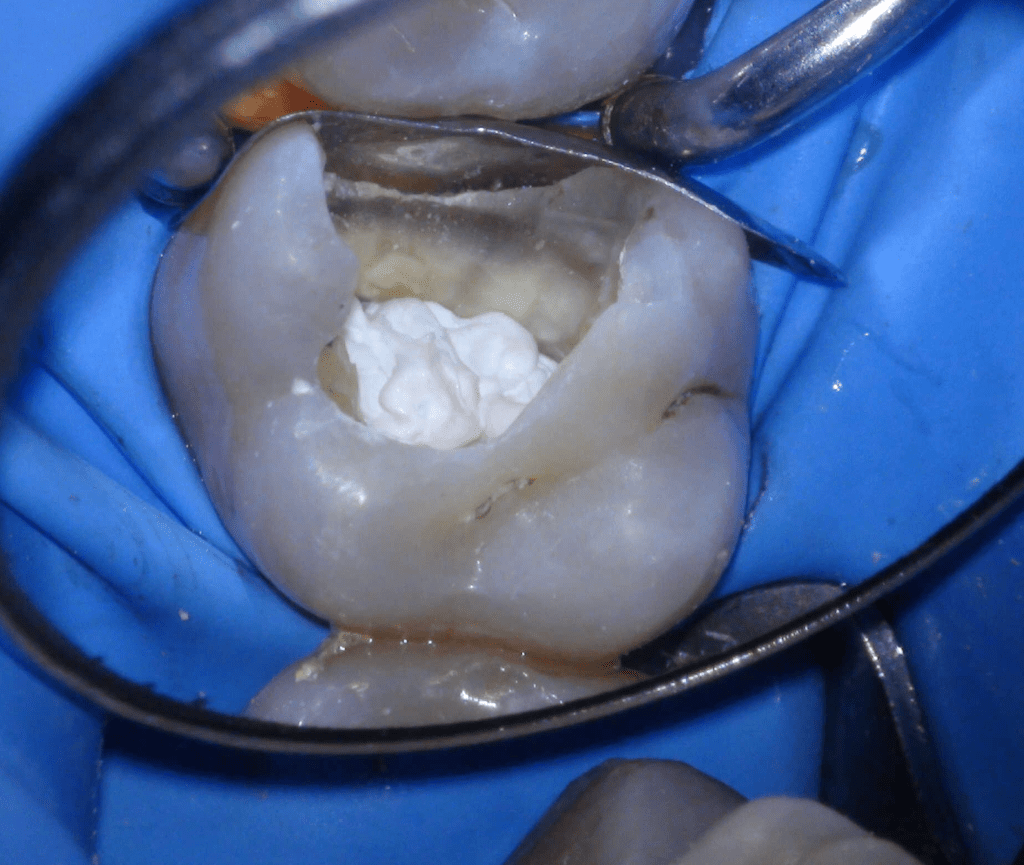

Diente fisurado tratable con endodoncia

Diente fisurado tratable endodoncia 2